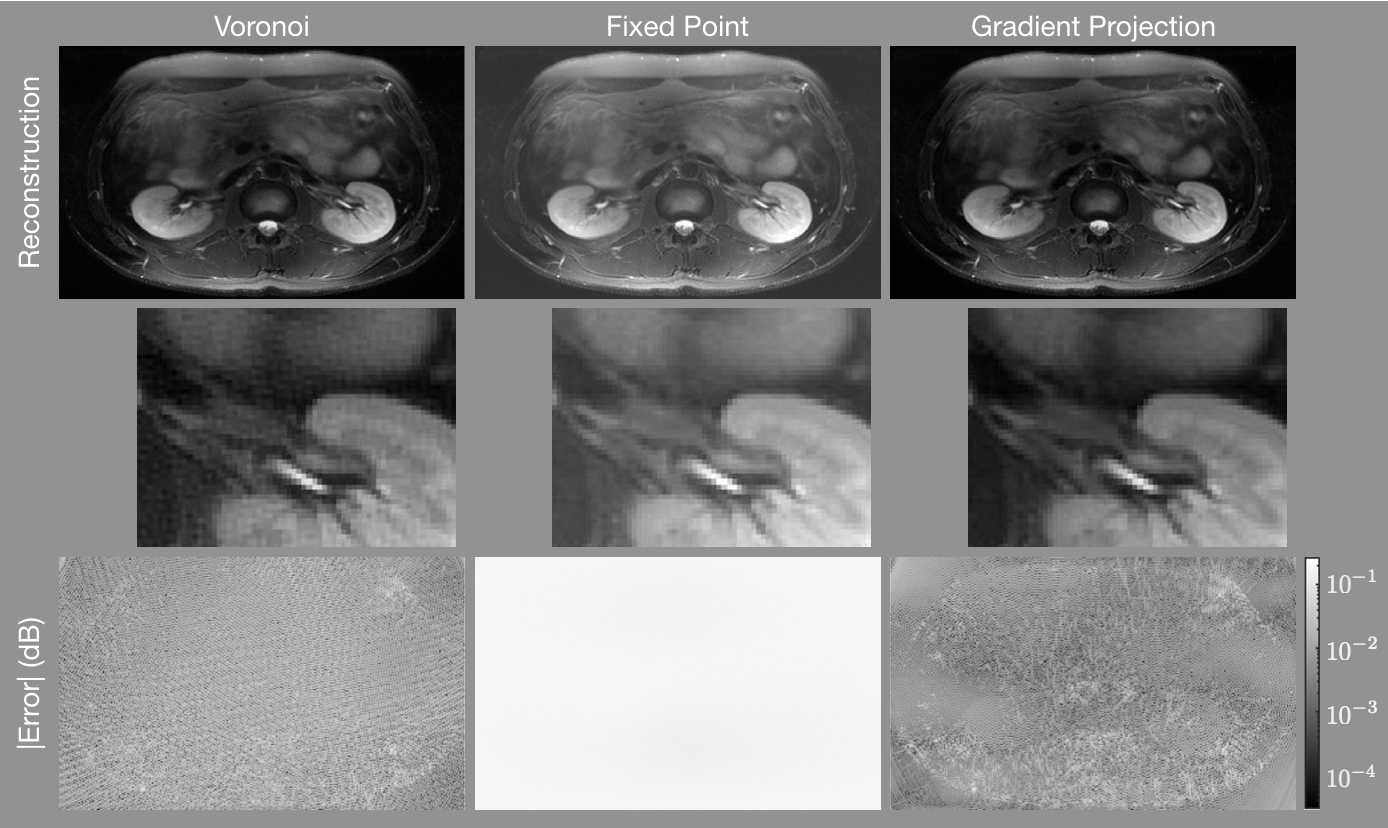

Figure 4 shows results for the abdomen. The top row shows the reconstructed images, the middle row shows a region centered near the left kidney zoomed into the white rectangle shown in Fig. 1b, and the bottom row shows the difference images. As with the numerical phantom, there are regions of the image with less error when using the gradient projection algorithm than when using the competing algorithms. The FP reconstruction yields an image that is too bright. Additionally, it alters the contrast of the image significantly, making regions of the center of the image much brighter than the true image. In the zoomed-in images, note that there is an erroneous high frequency block pattern super-imposed on the reconstruction with the Voronoi cell based weights that is absent in the GP reconstruction.

Refer to caption

Figure 4: Gridding reconstructions of the abdomen with density compensation values determine using (left) the areas of Voronoi cells, (center) the fixed-point iteration algorithm, and (right) the gradient projection algorithm. The first row shows the reconstructed images, the second row shows a zoomed into a portion of the image centered on the left kidney indicated by the white rectangle shown in Fig. 1b, and the third row shows the error of each pixel in decibels. The gradient projection algorithm has lower error in more portions of the image than the other techniques.